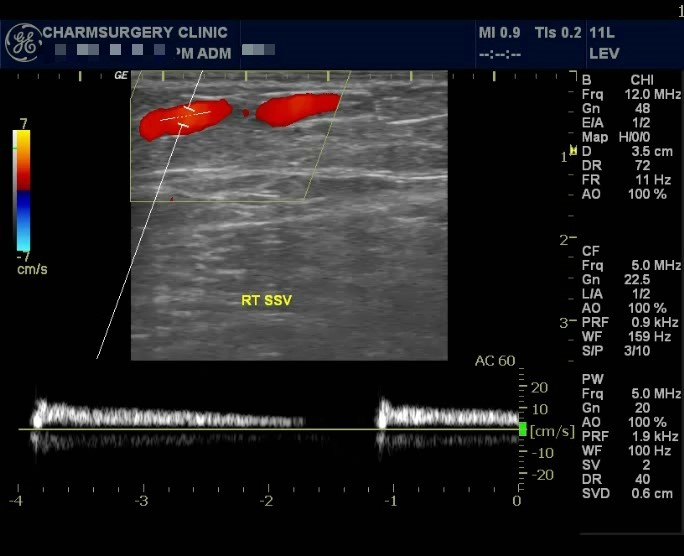

하지만 혈관초음파 검사 결과상

혈관의 확장 및 역류 소견이 관찰되고 있는 수술적응증에 해당되는 소견이었습니다